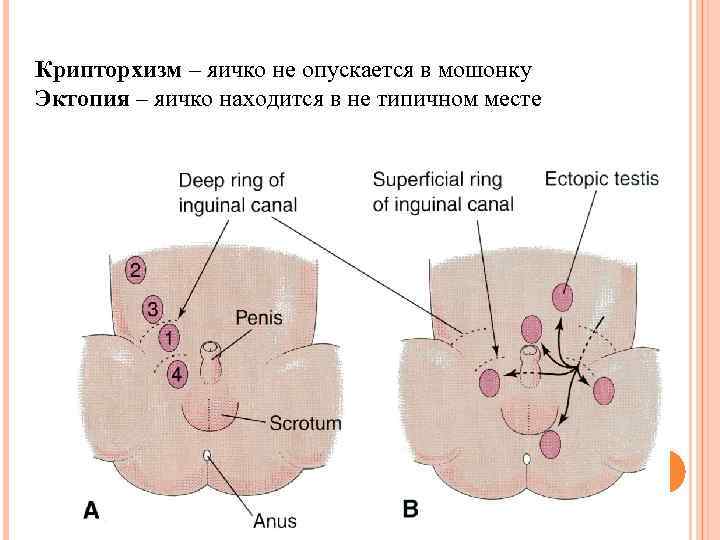

Крипторхизм – яичко не опускается в мошонку Эктопия – яичко находится в не типичном месте

Крипторхизм – яичко не опускается в мошонку Эктопия – яичко находится в не типичном месте

Крипторхизм – яичко не опускается в мошонку

Крипторхизм – яичко не опускается в мошонку